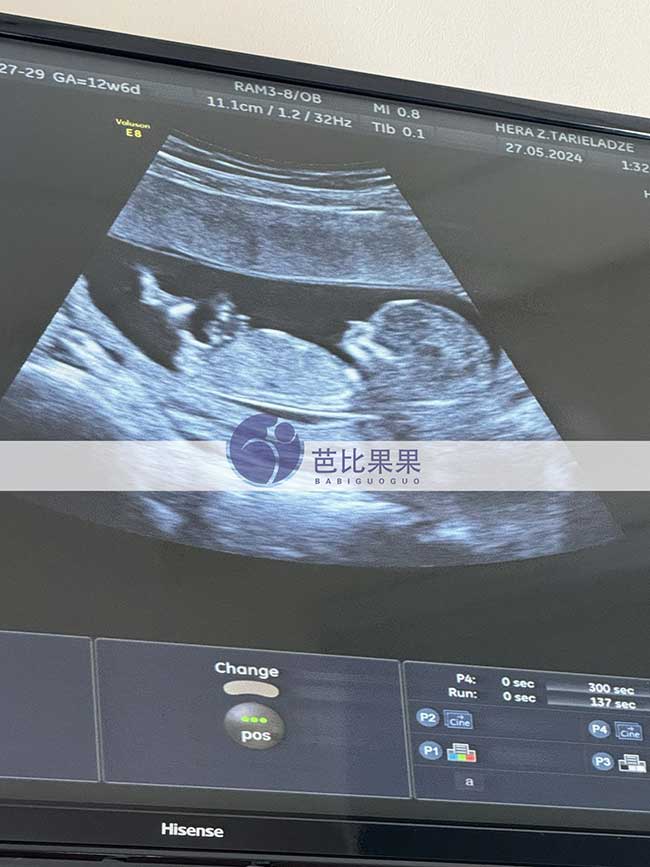

S先生在格鲁吉亚助孕的试管妈妈怀双胞胎到医院做B超

S先生在格鲁吉亚助孕的试管妈妈到医院做B超,腹内双胞胎宝宝发育的很好,已经孕12周多啦